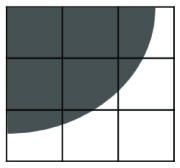

where is the mask of an ellipse parametrized by . As minimizing such a term is not straightforward, the authors optimize the energy functional iteratively, i.e. by finding the best for a fixed and then optimizing for a fixed . For complex shapes that are hard to parametrize, an alternative approach is to fit a shape template to the current segmentation as proposed in (Freedman and Zhang, 2005). Veksler (2008) proposed to incorporate a more general class of shapes, known as star shapes, into graph-based segmentation. In Veksler’s work, it is assumed that the center point () of the object is given. According to their definition, “an object has a star shape if for any point inside the object, all points on the straight line between the center and also lie inside the object” (Figure 13). The following pairwise term was introduced to impose the star shape prior:

| (33) |

This prior is particularly useful for segmentation of convex objects, e.g. optic cum and disc segmentation (Bai et al., 2014).